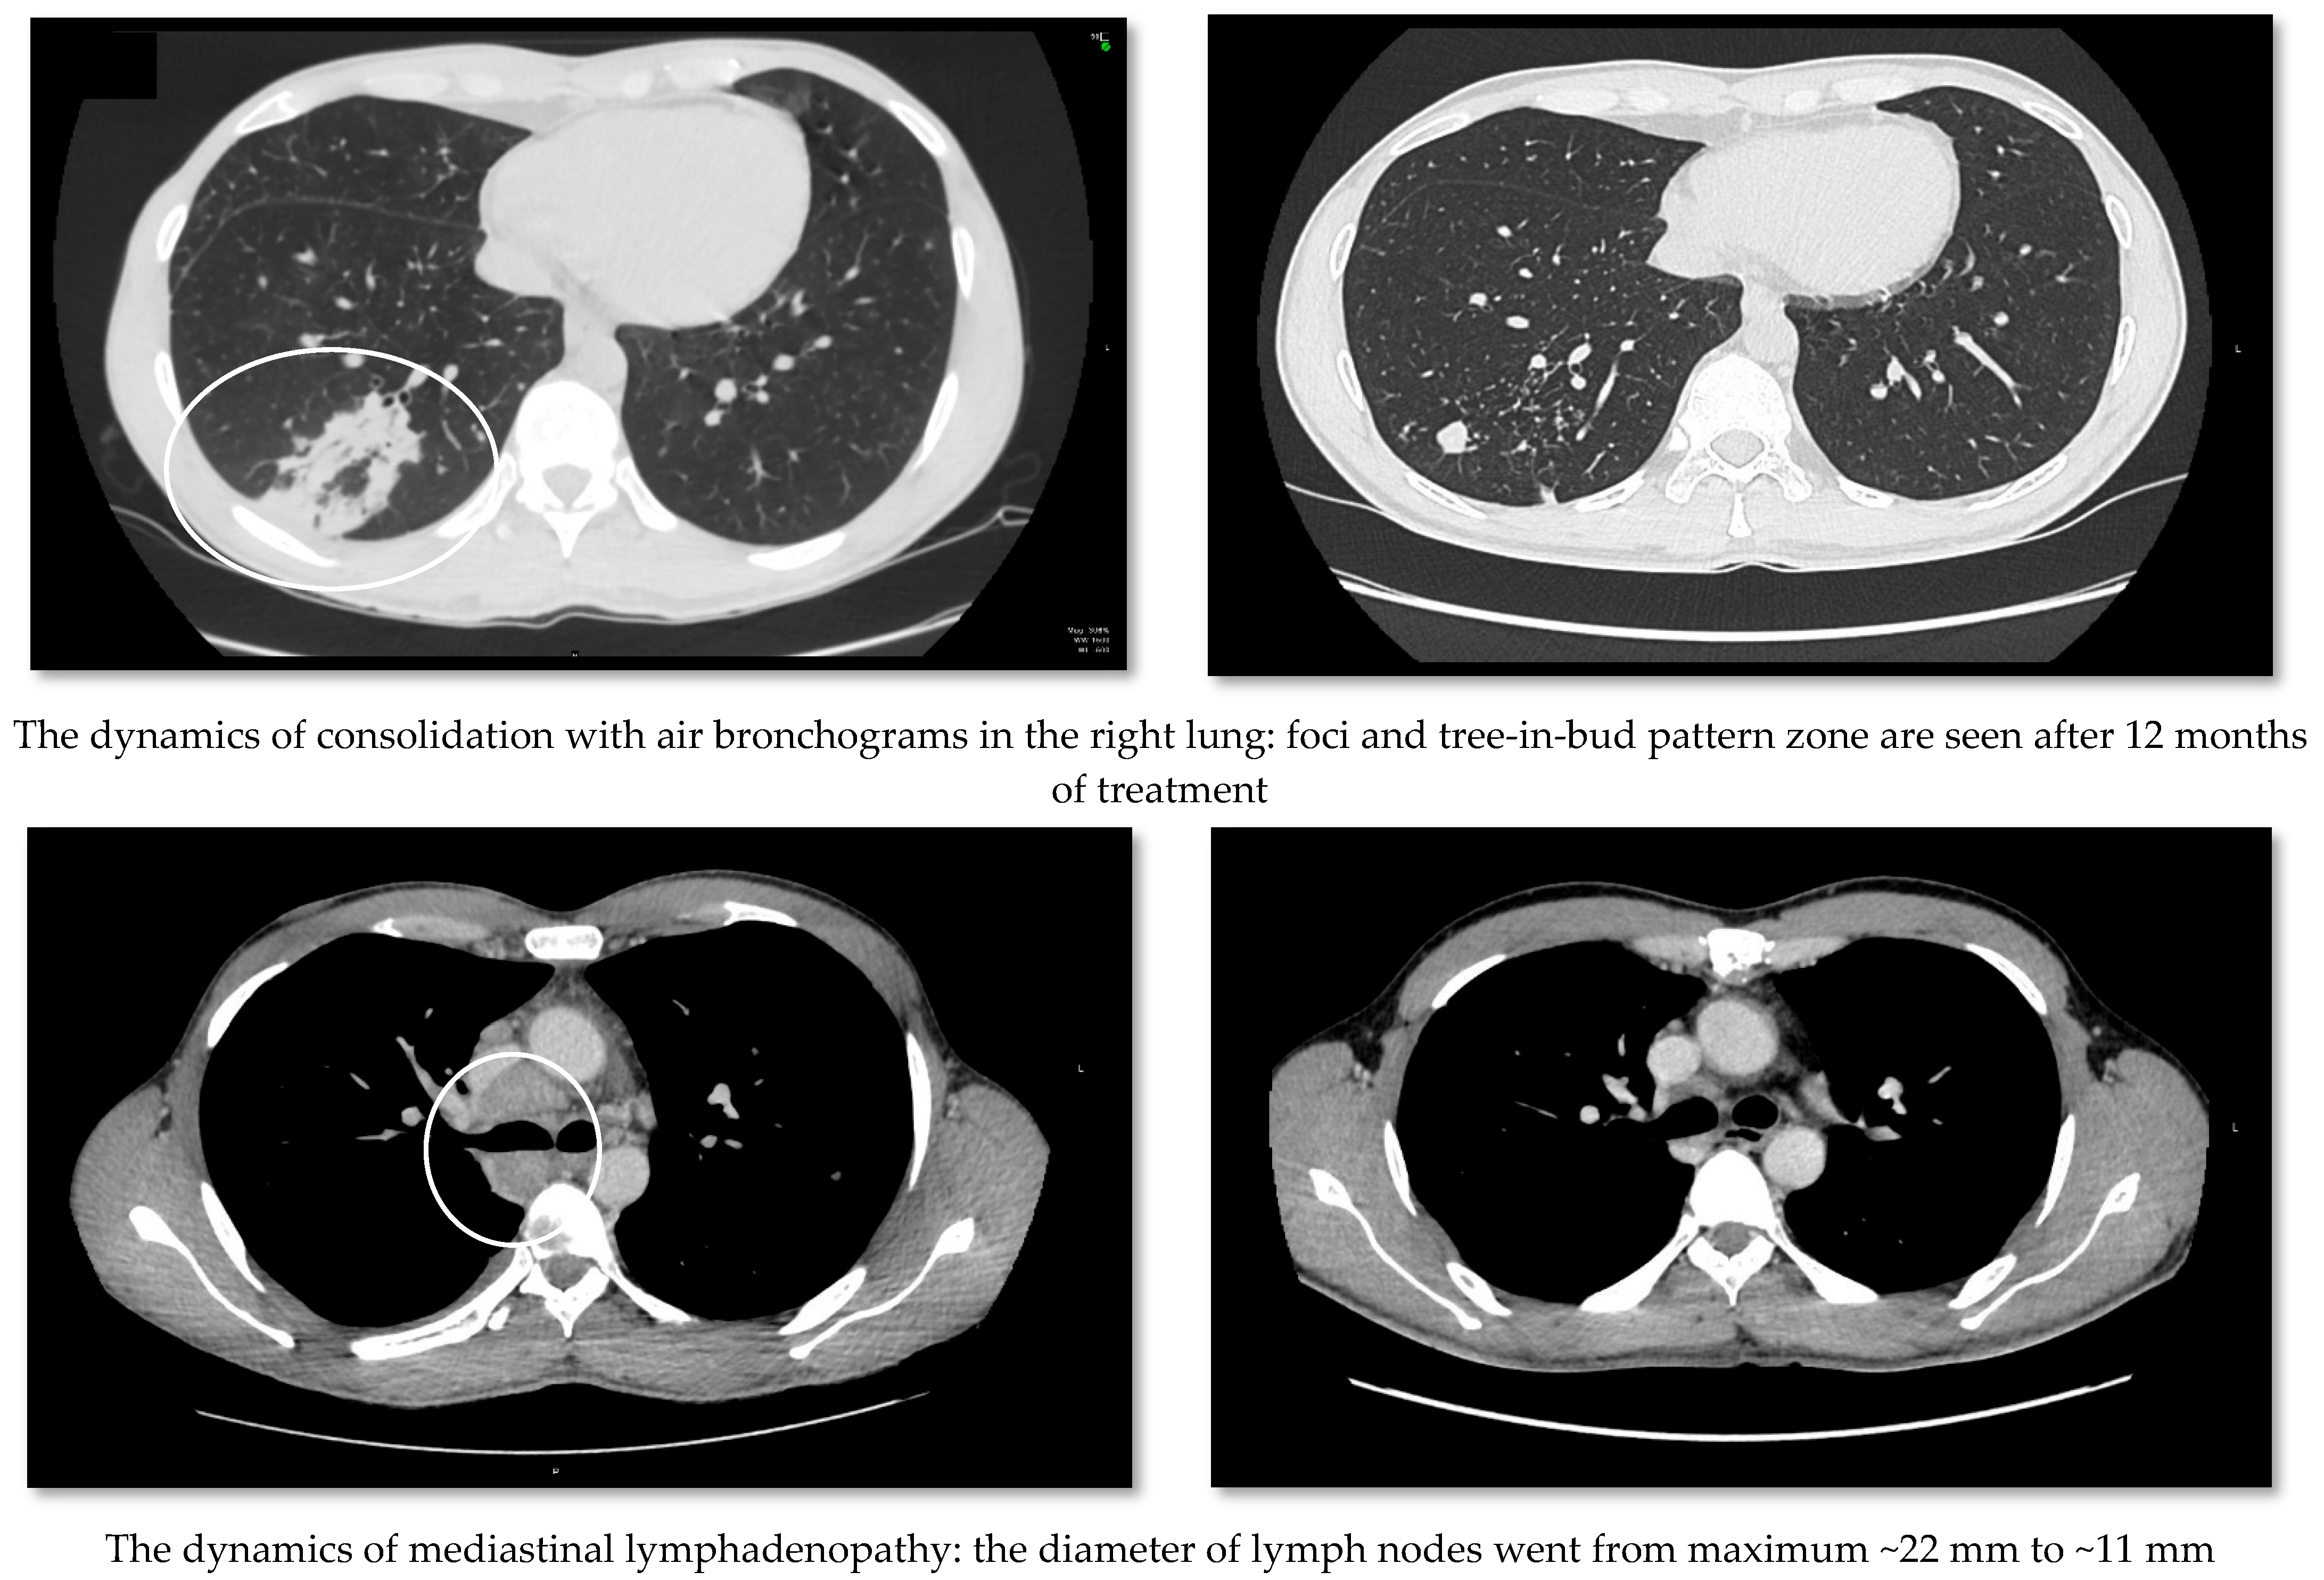

2. Case Report